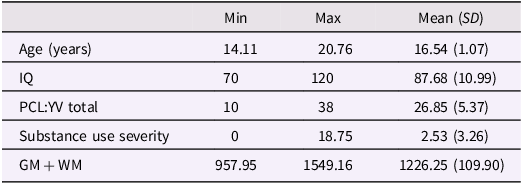

Table 1. Descriptive features n = 152 incarcerated male youth

The final analysis included n = 152 boys, excluding n = 18 for low IQ and n = 5 for TBI. Descriptive features of this sample are provided in Table 1. Substance use severity in this sample is described in Table 2, which accounts for those in the sample meeting criteria for problematic use of each substance, defined as three or more times per week for a minimum period of 1 month.

Table 2. Substance use in n = 152 incarcerated male youth